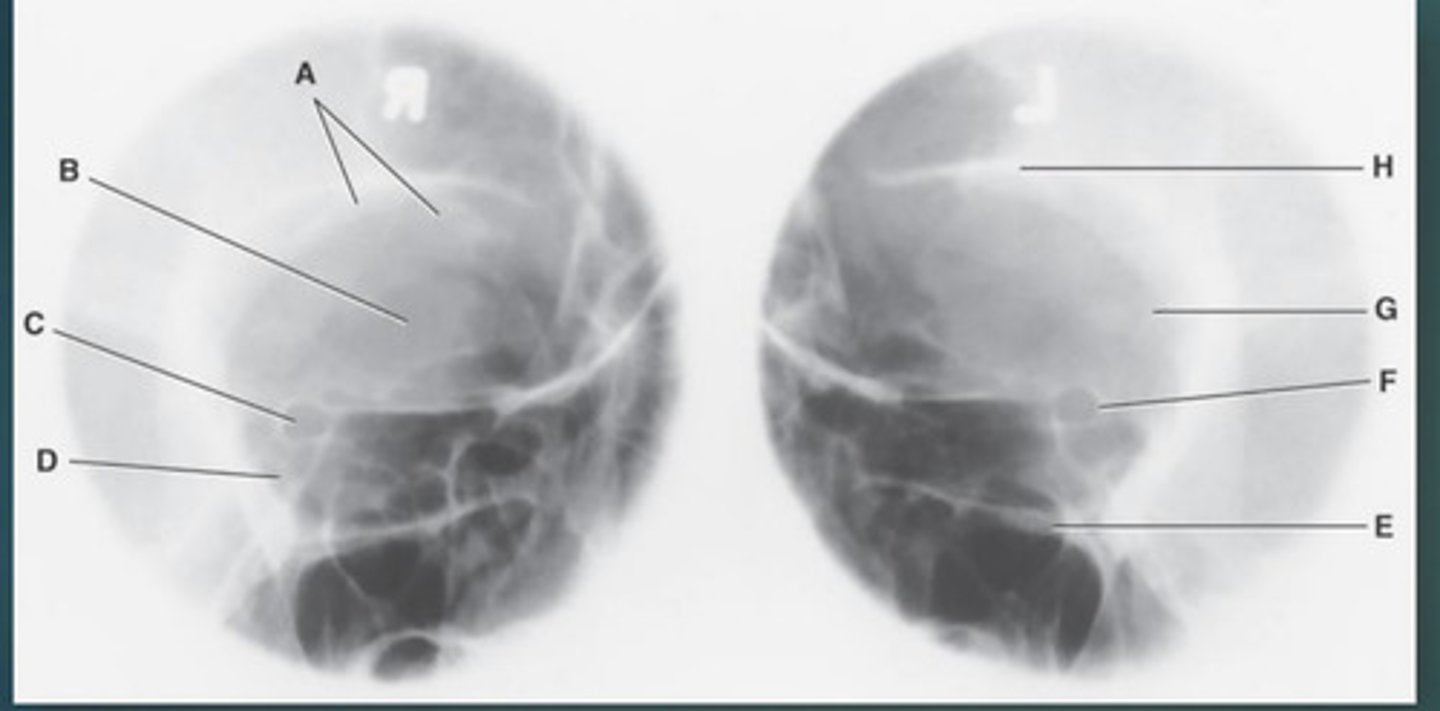

Lateral sinus

What position?

L. Orbital roofs

A.

L. Greater wings of sphenoid

B.

sella turcica of sphenoid

C.

L. Sphenoid sinus

D.

L. Rami of mandible

E.

L. Maxillary sinuses

F.

L. Ethmoid sinuses

G.

L. Frontal sinuses of frontal bone

H.